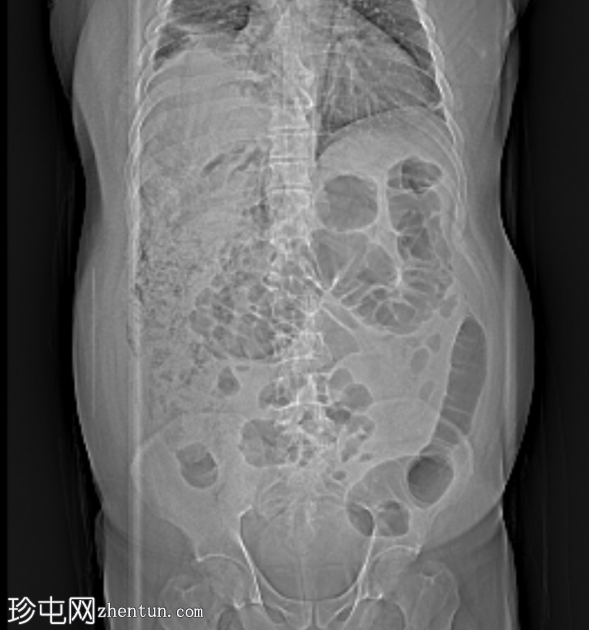

CT

定位扫描

可见阑尾后方炎症,阑尾尖端积液,肾后间隙可见大量气体,炎症延伸至肝周、腰大肌后方及腹壁筋膜平面,符合阑尾穿孔引起的广泛性坏死性筋膜炎的

影像

学表现。